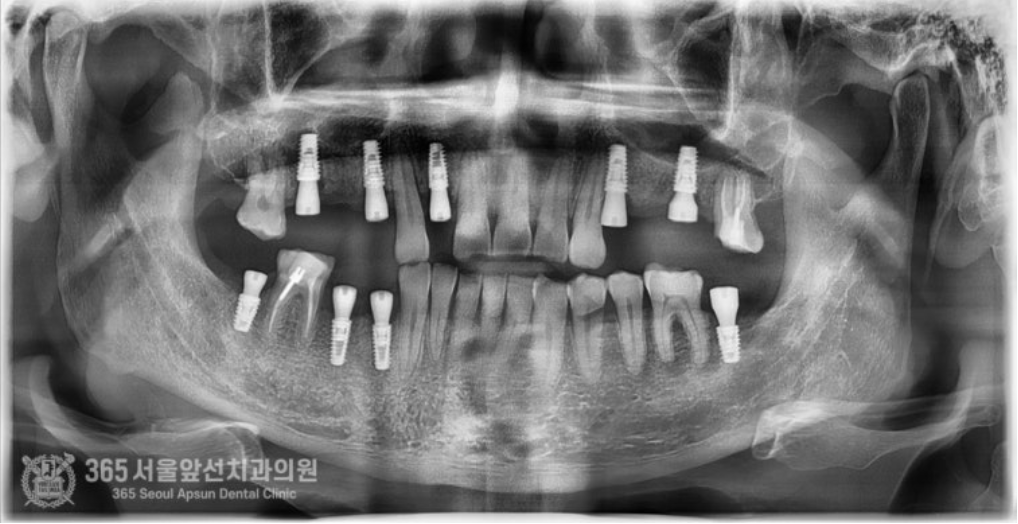

안녕하세요. 석바위시장치과 365서울앞선치과의원입니다. 오늘은 전체 임플란트 치료증례를 살펴보겠습니다. 예전에 치료해드렸던 환자분께서 소개해주신 환자분이십니다. 빵도 사다주시고 참 감사했던분이신데요 ㅎㅎ 촬영일시 : 2024.08.03. 처음 내원당시 상태는 이가 많이 없어서 제대로 밥을 먹을 수가 없어요. 잘 웃지도 못하구요. 이가 많이 없으셔서 식사도 불편하고 특히 사회생활에 불편감이 있으시다고 하셨습니다. 진단과정을 거쳐 발치할 치아는 발치하고 살려서 쓸 수 있는 치아는 살려쓰는 것으로 계획하여 치료를 진행하였구요. 촬영일시 : 2024.10.11. 임플란트가 모두 식립된 상태입니다. 치아가 없는 자리와 치아를 발치한 자리에는 임플란트를 식립하여 튼튼하게 보철물을 제작해드렸구요. 살려서 쓸 수 있는 치아는 신경치료 후 크라운으로 보강하여 마무리해드렸습니다 ㅎㅎ 치료기간은 대략 3~4개월 정도 걸렸습니다. 촬영일시 : 2025.01.12. 치료 종결 후 엑스레이 사진입니다. 임플란트가 반듯하게 잘 식립되었네요. 치아도 기존 치아색상과 조화를 이룰수있게 자연스러운 색조로 제작해드렸습니다ㅎㅎ 아주 만족하셨어요. 임플란트 치료하고 나서 인상이 확 바뀌었다는 얘기를 많이 들었어요. 이런 말씀을 해주실때마다 의사로서 뿌듯함을 느낍니다 ^^ 오늘은 소문을 듣고 내원하신 환자분을 전체 임플란트 치료를 통해 만족시켜드린 증례를 소개해봤습니다. 앞으로도 좋은 증례로 찾아뵙겠습니다. 석바위시장치과 365서울앞선치과의원이었습니다. 감사합니다. [ 치료기간: 2024년 8월3일 ~ 2025년 1월 12일 ] ※ 365서울앞선치과의원의 모든 포스팅은 각 진료과 의료진이 직접 작성합니다. 365서울앞선치과의원 블로그의 임상 케이스 게시물은 환자분께 의학적으로 정확하고 상세한 정보를 드리기 위해 각 진료과 의료진이 직접 작성하며, 모든 증례 사진은 본원 의료진이 직접 시술한 증례를 촬영한 것으로, 의료법 제23조, 제56조에 의거하며 환자분의 동의를 얻어 포스팅에 사용하였습니다. 또한 해당 케이스는 본 환자분의 치료 결과이며, 환자 상태에 따라 치료의 결과는 달라질 수 있습니다. |